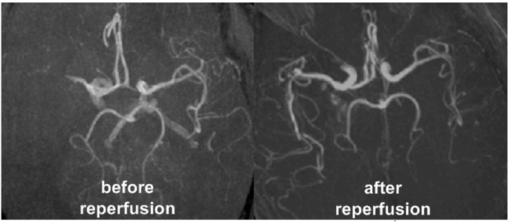

Figure 4 shows angiographic images before and after arterial reperfusion in one stroke patient. The multinuclear 23Na/1H MRI data set for the same patient is presented in figure 5. The quantitative results for the investigated stroke patient are summarized in table 2.

Figure 4. Axial maximum intensity maps of arterial blood flow weighted 1H MR images before (left) and after arterial reperfusion (right) as acquired for one stroke patient. Excellent image resolution was achieved with double-tuned 23Na/1H head resonator at 3T.